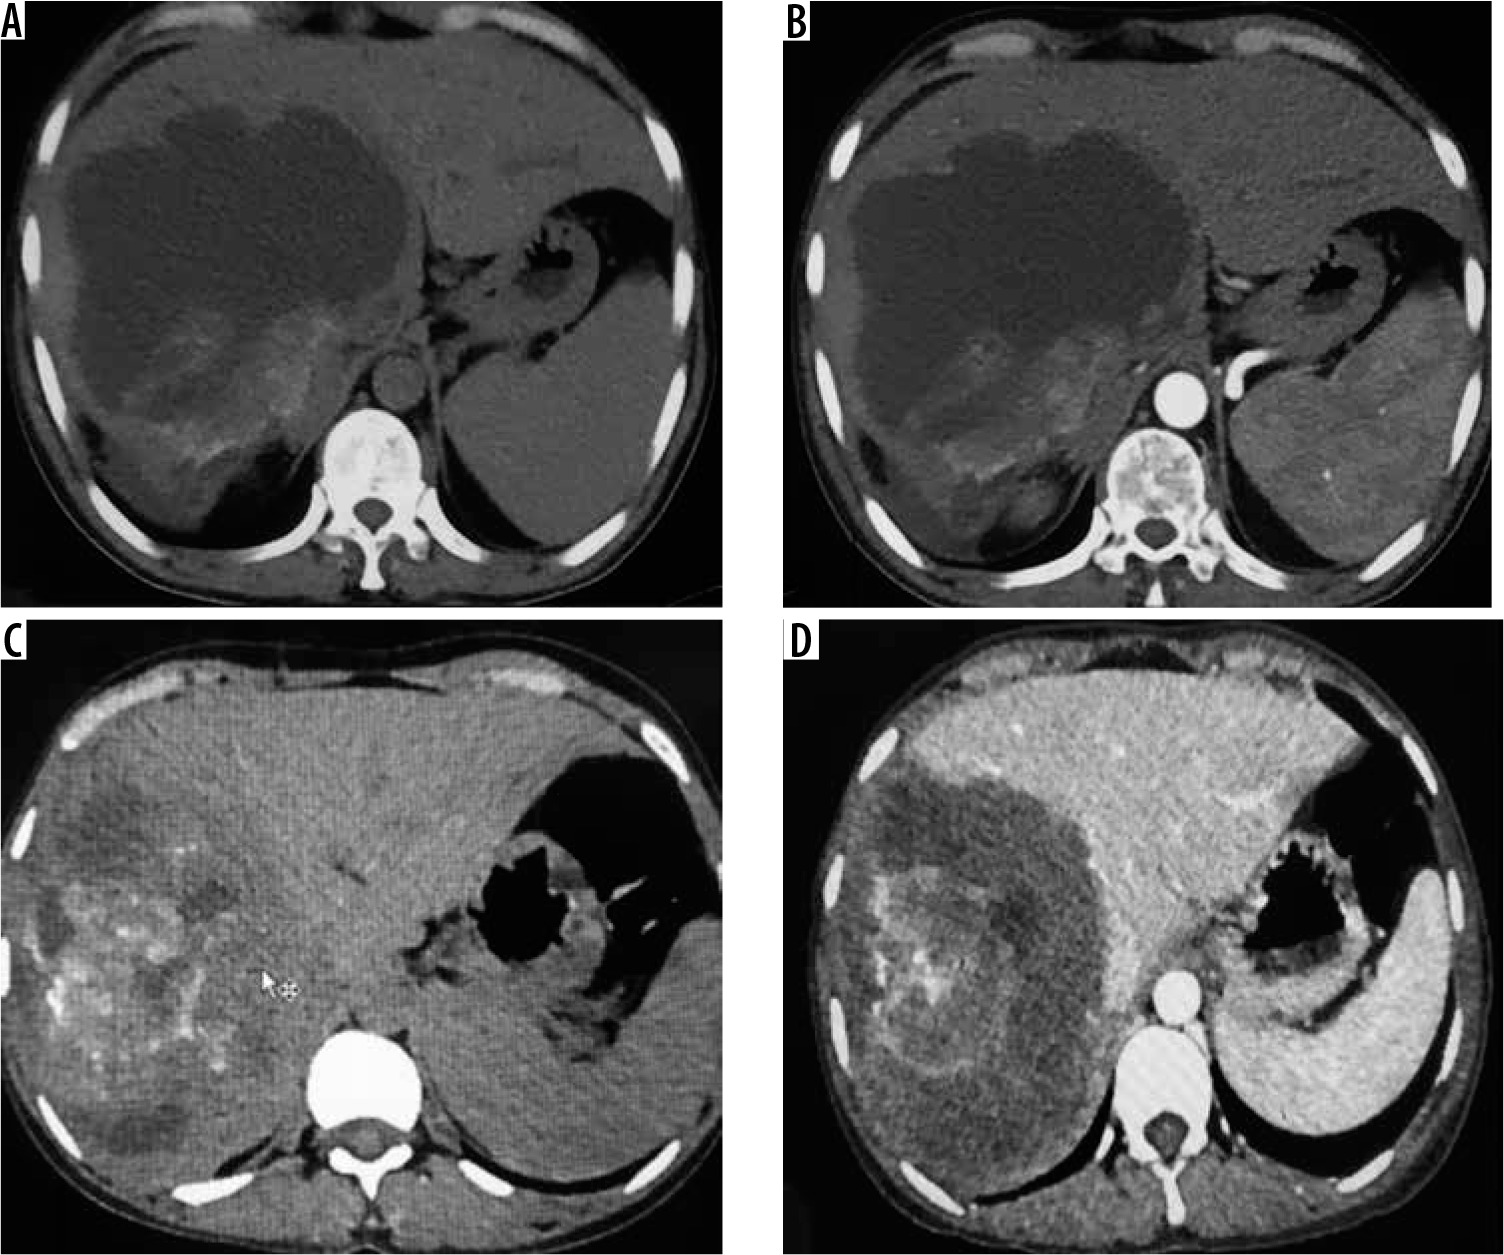

Figure 4

A) Non-contrast axial computed tomography (CT) image in a patient showing large thick-walled cystic mass in segment VII and VIII with peripheral calcification. B) Corresponding arterial phase axial CT image reveals absence of any enhancement. C) Axial non-contrast CT image in a different patient shows large heterogeneous density mass lesion in segment VII and VIII with sheet-like central calcification. D) Corresponding post-contrast axial CT image reveals no enhancement of the mass. The lesion is seen infiltrating the right and middle hepatic vein (P3 disease)

Figure 5

A) Axial non-contrast computed tomography (CT) image through upper abdomen reveals a large heterogeneous mass involving whole right lobe with scattered matrix calcifications with capsular retraction. Portal phase contrast-enhanced axial CT images (B, C) at slightly different levels reveal no enhancement of mass. B, C) Mass shows infiltration of hepatic hilum with encasement of portal vein, common bile duct, and hepatic artery. D) Sagittal post-contrast CT image clearly shows encasement of intra hepatic IVC (P4 disease)